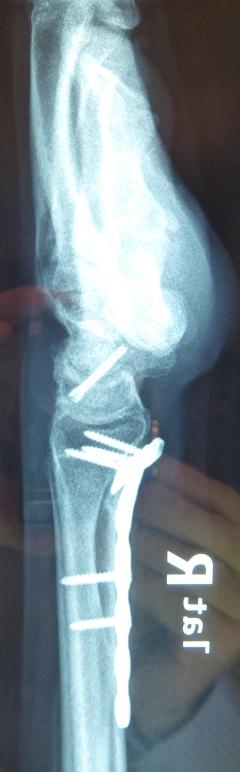

Η αντιμετώπιση της ψευδάρθρωσης του σκαφοειδούς είναι πάντοτε χειρουργική. Με ραχιαία ή παλαμιαία προσπέλαση αποκαθίσταται ο άξονας του σκαφοειδούς και σταθεροποιείται το σκαφοειδές με ειδική βίδα ή βελόνες, με παράλληλη τοποθέτηση οστικών μοσχευμάτων. Μπορεί επιπλέον να γίνει και οστεοτομία κλειστής σφήνας του περιφερικού άκρου της κερκίδος. Στις περιπτώσεις άσηπτης νέκρωσης το μόσχευμα πρέπει να είναι αγγειούμενο – για να προσδώσει αιμάτωση στο νεκρωμένο κεντρικό τμήμα – και λαμβάνεται με μικροχειρουργικές τεχνικές από το περιφερικό τμήμα της κερκίδος ή από άλλα τμήματα του σώματος

Διεγχειρητικά